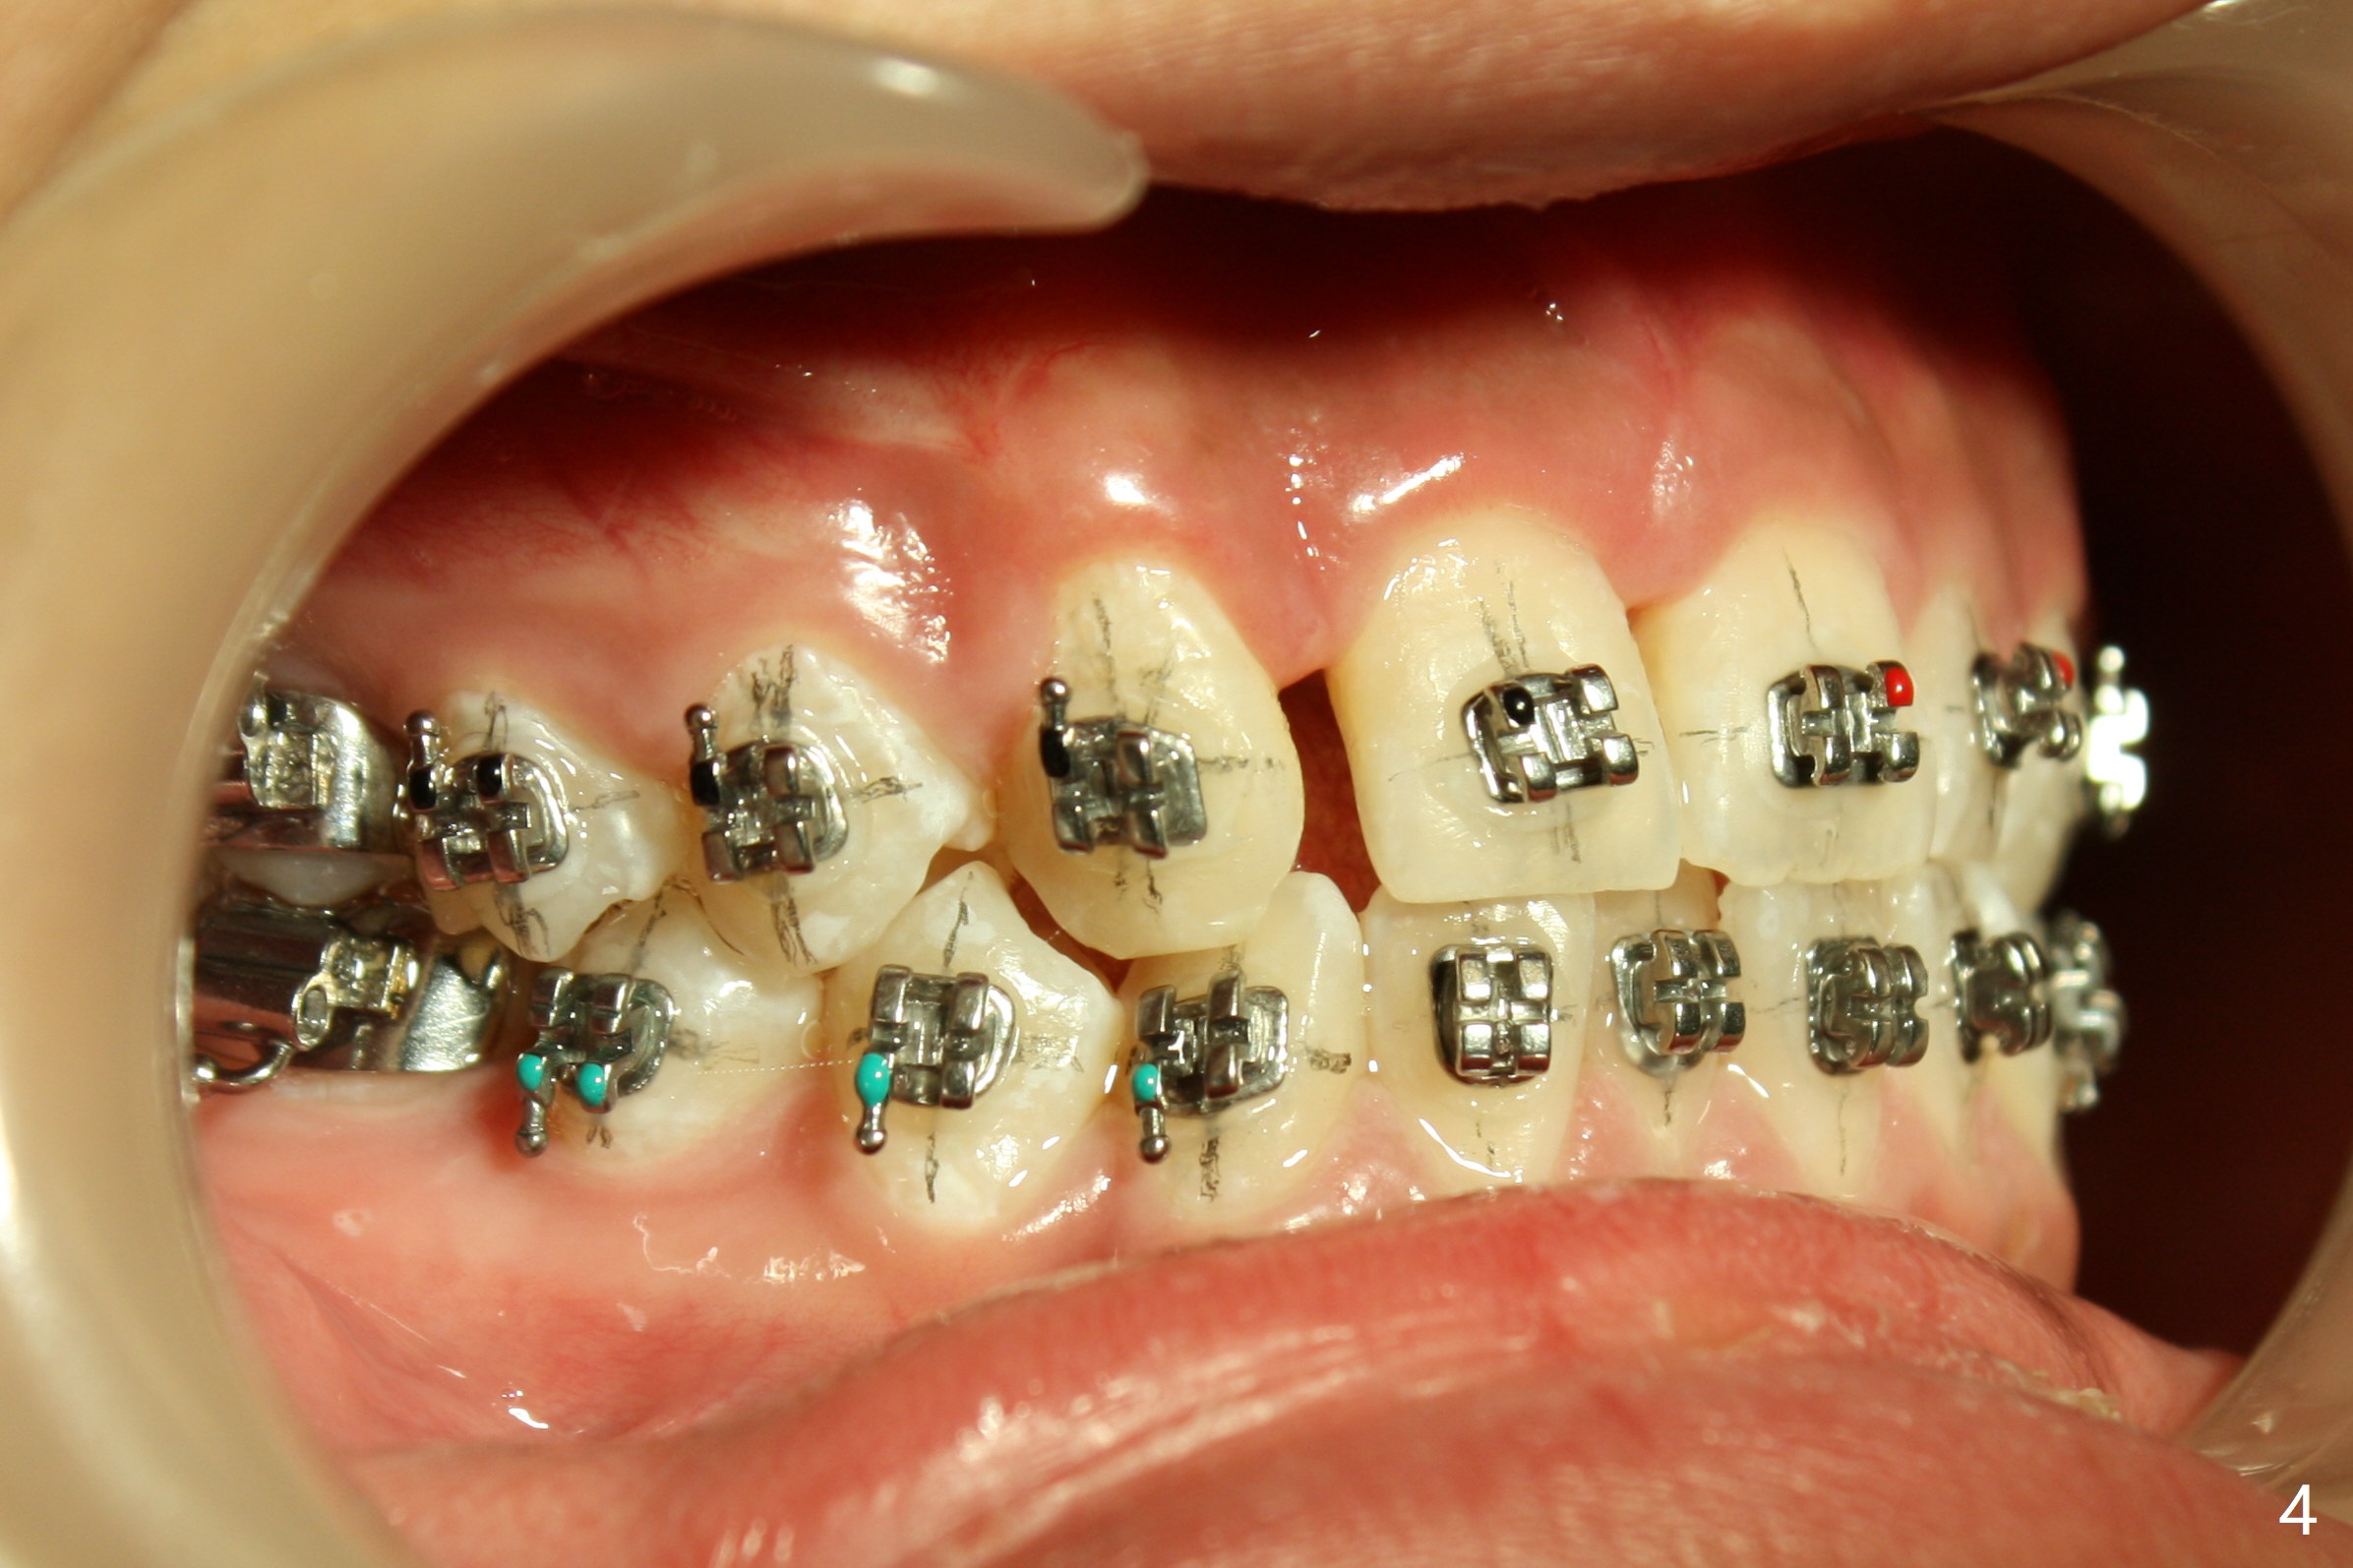

Preop cephalometric tracing shows normal skeletal relationship (Fig.1,2). The upper dental midline deviates to the right (Fig.3). To control root torque, UR1,3 bracketing is intentionally placed off (Fig.4,5, as compared to Fig.6). Take PA for UR1/3 next visit. In fact PA has not been taken. The patient has complained of UR1 turning (mesial incisal edge elongation due to bracket off placement) since the 1st appointment post banding. On the 3rd appointment (2 months 12 days post banding with 18 ss wire), the mesial incisal edge of UR1 and the distal incisal edge of UR3 are trimmed; 18 wires are reused with addition of an open coil spring between UR1-3 (Fig.7). Extra diastemata have appeared mesial and distal to UL1 (Fig.8 *), creating room to correct the upper dental midline shifting. PA is taken 5 months post banding (Fig.9). The roots of neighboring teeth are parallel with new bone formation behind. The mesiodistal space is similar to that of the tooth #10 following consolidation of diastemata on the left. More space is gained 12 months post banding (Fig.10).